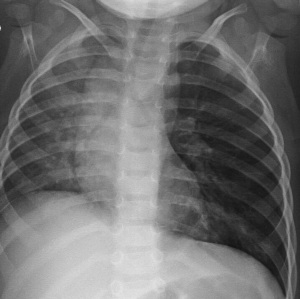

Image IQ Quiz: Patient Presents with Shortness of Breath and Distress

March 2nd 2021

What is your diagnosis of a young child who presents with shortness of breath and distress?

• Image IQ Quiz: Patient Presents with Shortness of Breath and Distress

Published: March 2nd 2021 | Updated: